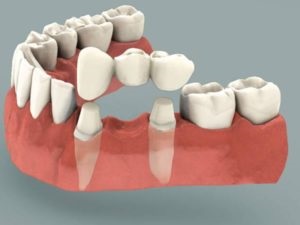

Construcția coroanelor artificiale secvențiale, fixate între ele, a fost numită pod.

Aceste structuri sunt fabricate din materiale diferite. Ele sunt atașate la două dinți de sprijin, înlocuind uneori toată dentiția.

Podul, fixat pe dinții de susținere, constă din coroane, dintre care ultimul este gol, sunt purtați pe dinții ascuțiți ascuțiți. Coroanele rămase sunt făcute integral pentru o mai mare rezistență a structurii.

Podul poate fi fixat pe implanturi sau pe dinți vii. Lungimea acesteia depinde de numărul de dinți pe care îi înlocuiește.

Diferența dintre podul implanturilor este că dinții pacientului și implanturile implantate în maxilar nu sunt folosite ca suporturi. Acestea ar trebui să fie de cel puțin două, în funcție de numărul de dinți care ar trebui să înlocuiască podul.